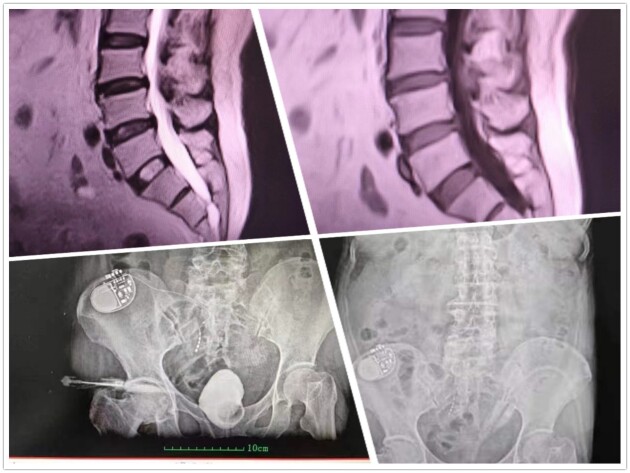

根據(jù)肖教授的經(jīng)驗(yàn),類似情況主要就是支配膀胱會(huì)陰的神經(jīng)束或神經(jīng)根受壓所致,這和坐骨神經(jīng)疼是一個(gè)道理,神經(jīng)受壓位置不同罷了。檢查結(jié)果出來后,與肖教授的分析果然相差無幾,通過脊髓核磁共振檢查,顯示患者隱性脊柱裂和骶管囊腫,異常增厚硬化的黃韌帶嚴(yán)重壓迫硬膜腔終端骶神經(jīng)束,進(jìn)而導(dǎo)致一系列病癥發(fā)生。同時(shí)經(jīng)尿動(dòng)力檢查,這位患者膀胱僅能灌入60ml,逼尿肌過度頻繁收縮,遠(yuǎn)超普通的OAB,這也是唯一有肯定療效的骶神經(jīng)刺激器置入適應(yīng)癥,患者還患有輕度的DESD(外括約肌協(xié)同失調(diào))。確認(rèn)病根病源后,肖傳國(guó)教授親自來到手術(shù)室為患者實(shí)施手術(shù)。先行骶管探查,找準(zhǔn)部位后再行囊腫切除和黃韌帶切除手術(shù)。由于這類神經(jīng)源性膀胱的骶神經(jīng)尚未完全壓榨脫失萎縮,肖教授認(rèn)為絕大部分情況并不需要實(shí)施肖氏反射弧手術(shù)。